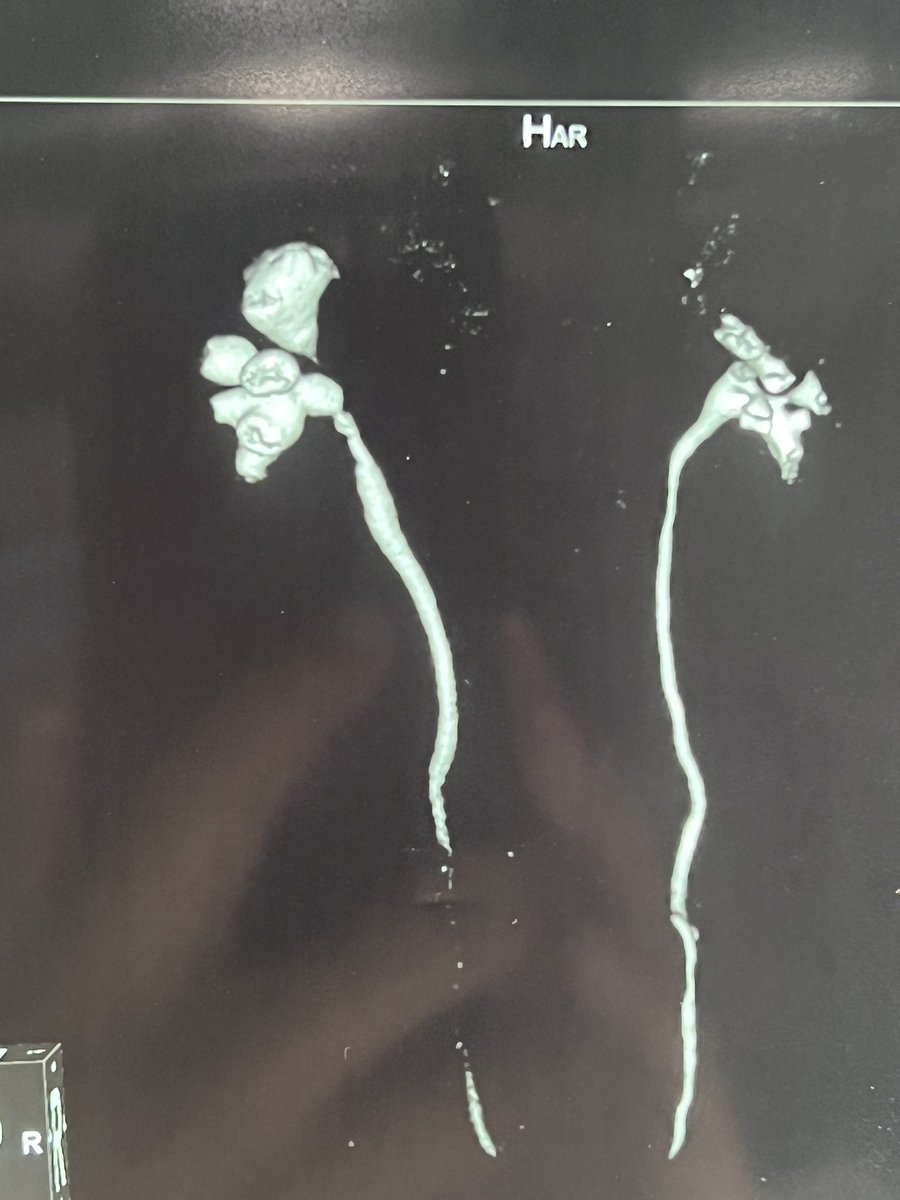

Recons can provide beautiful calyceal anatomy! Endourology Academy PETRA Endourological Society T&T Endourology Guido Giusti S K Pal #PERC NCCT v CECT for PERC your view!

“ I told you I will not need surgery ” . 😲🤔😱APIS KidneyStone Institute, TFL EndoUrology Center Endourology Academy mohamed elshazly Endourological Society Saeed Bin Hamri Kemal Sarıca Grand Rounds Urology #17 mm /15 mm !